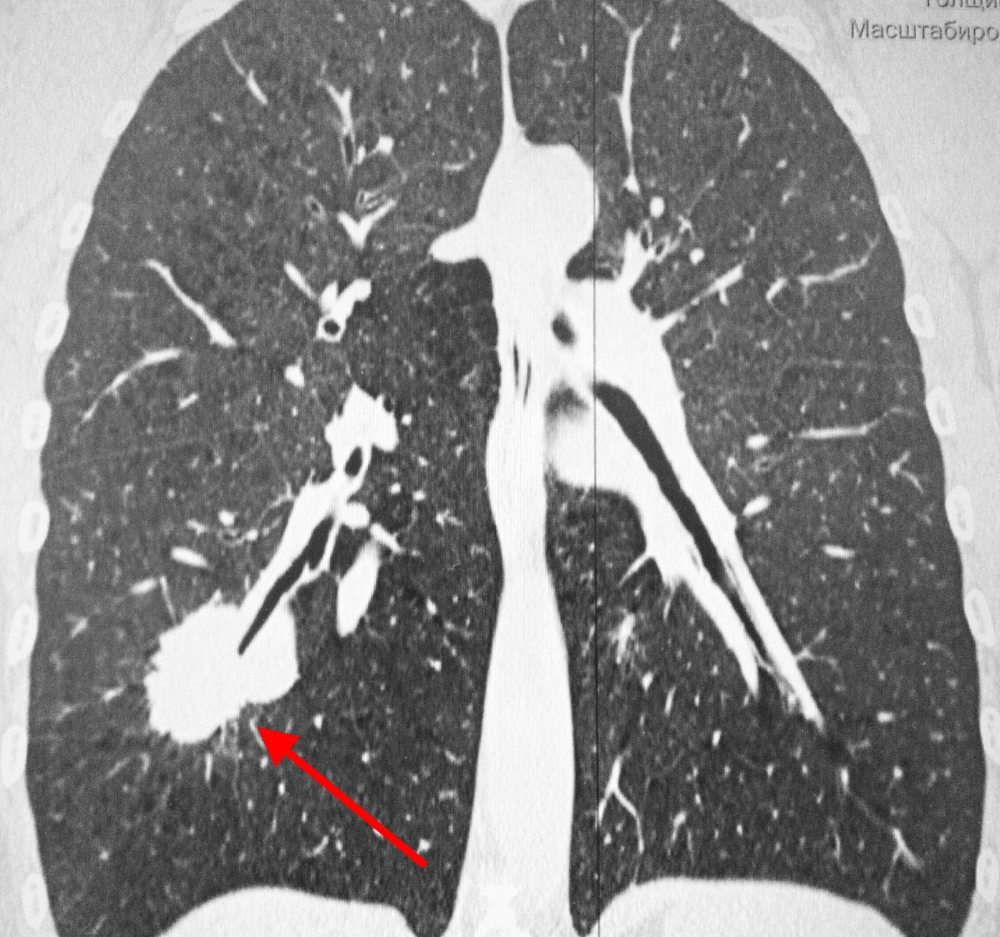

Фотографии и снимки КТ легких без контрастных веществ